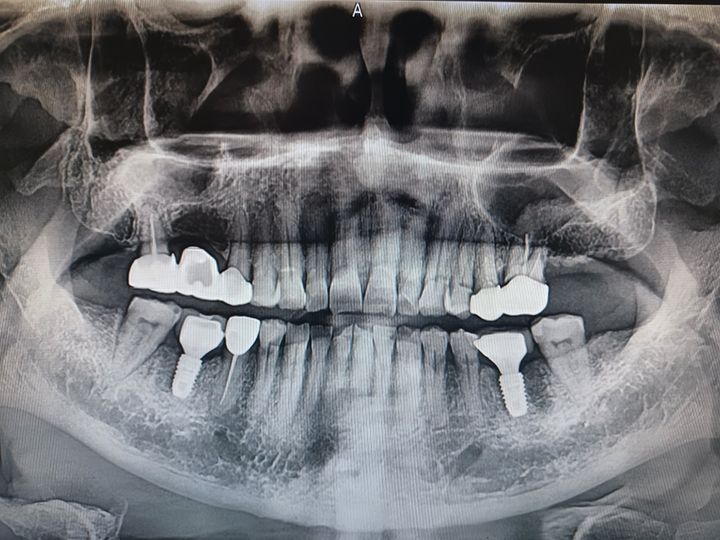

ハル歯科医院は、最先端のインプラント歯科治療に特化したクリニックです。代表のジョー・ハング院長は日本の神奈川歯科大学を卒業し、両国での歯科医師免許を保持。さらに、韓国で専門医資格を取得し、口腔外科など高度な手術経験も豊富です。すべての治療を院長自らが行う専任診療制を採用しており、流暢な日本語で対応可能。「デジタルインプラント」や「無削除ラミネート」などの最新のデジタル歯科治療を、日本の約半額で受けられます。仁川・金浦空港から乗り換えなしで行ける孔徳(コンドッ)駅すぐとアクセスも良好で、旅行者にも便利な立地となっています。

インプラント

匿名さん

日本でインプラント施術を行う予定でいましたが、色々と調べた結果、価格面でこちらで行うことを決めました。

先生との会話も日本語で行えて、海外で施術を受けるという当初の不安は無くなりました。

施術の内容や予算も相談して決められたので安心できました。また継続して訪問させていただこうと思います。

海外での初めてのインプラント治療、不安で何回もどうしようか考えた結果こちらの歯科でやって頂く事を決めました。LINEで何度も連絡を取らせて頂き

分からない事、不安な事、細かい事まで色々質問させて頂き2泊3日と言う短期間の旅行の中で

インプラントの埋め込みまで済ませて頂きました。先生が日本語で丁寧に説明してくれ安心して治療を受ける事ができました。

どこまでインプラントを埋め込んだら良いか先生からの提案、説明をお聞きした上でわたし自身の予算などある為自分の希望を話させて頂き

今できる中で希望通りの治療をして頂きました。